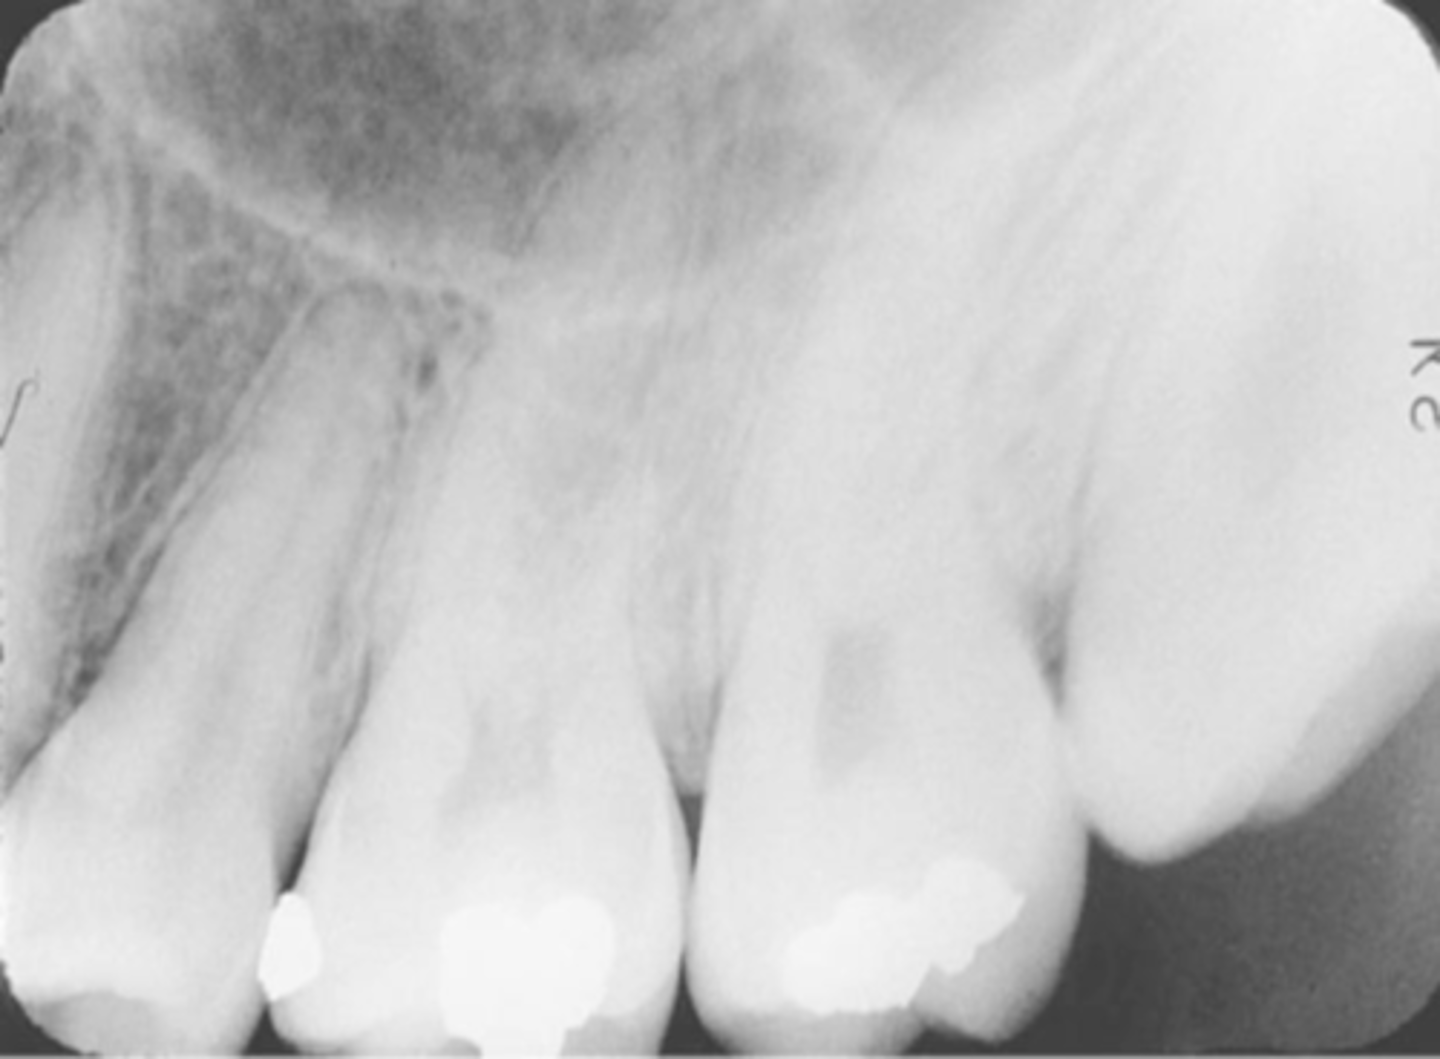

Overlapped Contacts

On a dental image, the area where the contact area of one tooth is superimposed over the contact area of an adjacent tooth

Incorrect Horizontal Angulation

-Overlapped contacts

-CR was not directed through the interproximal spaces, resulting in the proximal surfaces of adjacent teeth appear overlapped in the PA.

-Occurs in both paralleling and bisecting technique

-To prevent direct the x-ray beam through the interproximal regions

Incorrect Horizontal Angulation -->Bite-Wing

-CR was not directed through the interproximal spaces.

Tube Head & PID-->Overlapped teeth Contact

Cause - misdirecting the beam through the contacts, the x-ray beam/PID not perpendicular to the image receptor, Not positioning the image receptor parallel to the teeth

Correction - Move either mesial or distal depending on the mistake.

"Move toward it to fix it"